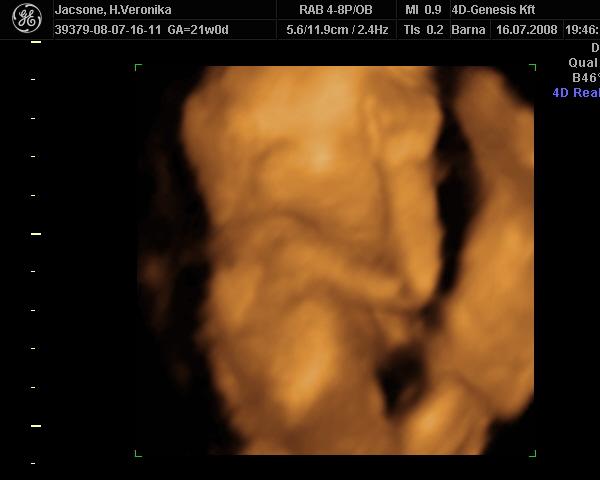

Donci-Bori remekül van, a doki mérése szerint 16 hetes-a vonalzóm szerint 17

.

A 12 hetes uh minden rendben találtak, legközelebb a 18 hetes genetikain láthatom megint.